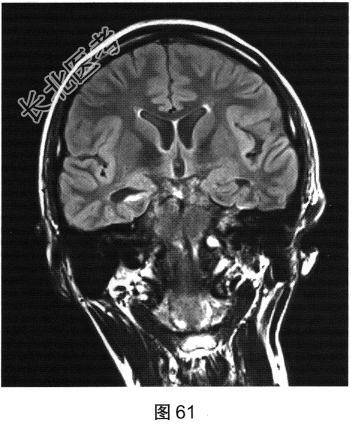

- 多项选择题2.[提示]患者行颅脑MRI检查,见图60、图61。MR检查可见哪些阳性影像学表现( )

A、右侧海马形态萎缩

B、右侧海马T2FLAIR信号增高

C、左侧颞叶皮质萎缩,脑沟增宽

E、左侧海马T2FLAIR信号增高

F、左侧海马形态萎缩

G、右侧颞叶皮质萎缩,脑沟增宽